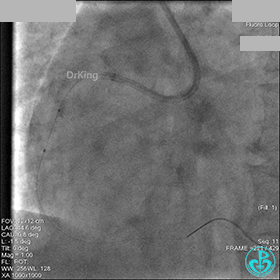

AL 1.0指引导管到位,简单短时尝试导丝不能顺利通过前降支或回旋支病变。改变策略处理右冠脉病变,计划植入2枚支架。AL指引导管到位,Sion blue导丝到达右冠脉远端。导丝通过后1.5mm及2.5mm球囊14~16atm充分扩张中段病变。

右冠脉中段充分扩张后欲植入3.5×38mm支架时,支架难以通过中远段扭曲处,且指引导管、导丝弹出飞扬。反复尝试导丝重新到达右冠脉远端时通过不顺利,局部造影剂滞留,远端血流接近3级。